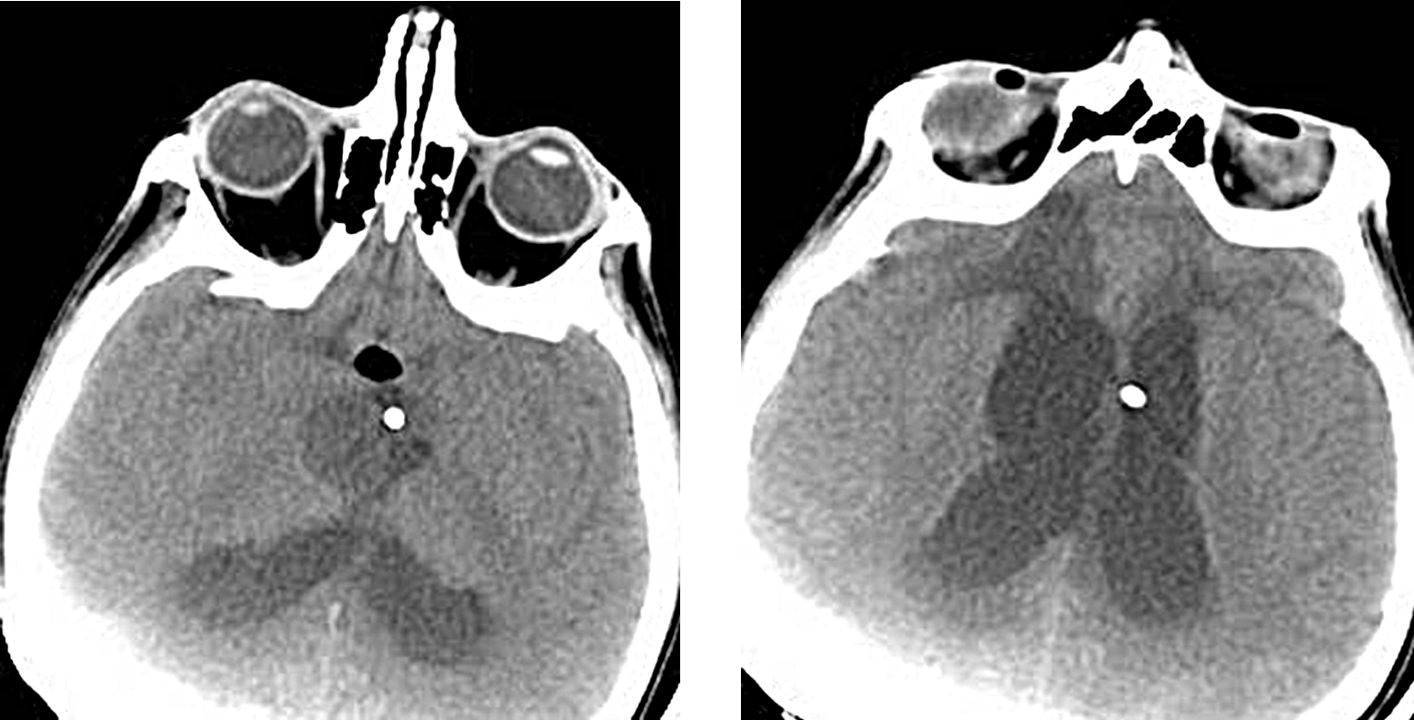

На контрольной компьютерной томограмме головного мозга выявлялось уменьшение размеров кистозного образования и степени гидроцефалии (рис. 2А, Б).

Рис. 2. Компьютерная томограмма пациента Р-ва после стереотаксической установки резервуара Оммайя в кисту краниофарингиомы; отмечается уменьшение размеров кисты и степени гидроцефалии

2. Рис. 2. Компьютерная томограмма пациента Р-ва после стереотаксической установки резервуара Оммайя в кисту краниофарингиомы; отмечается уменьшение размеров кисты и степени гидроцефалии | |